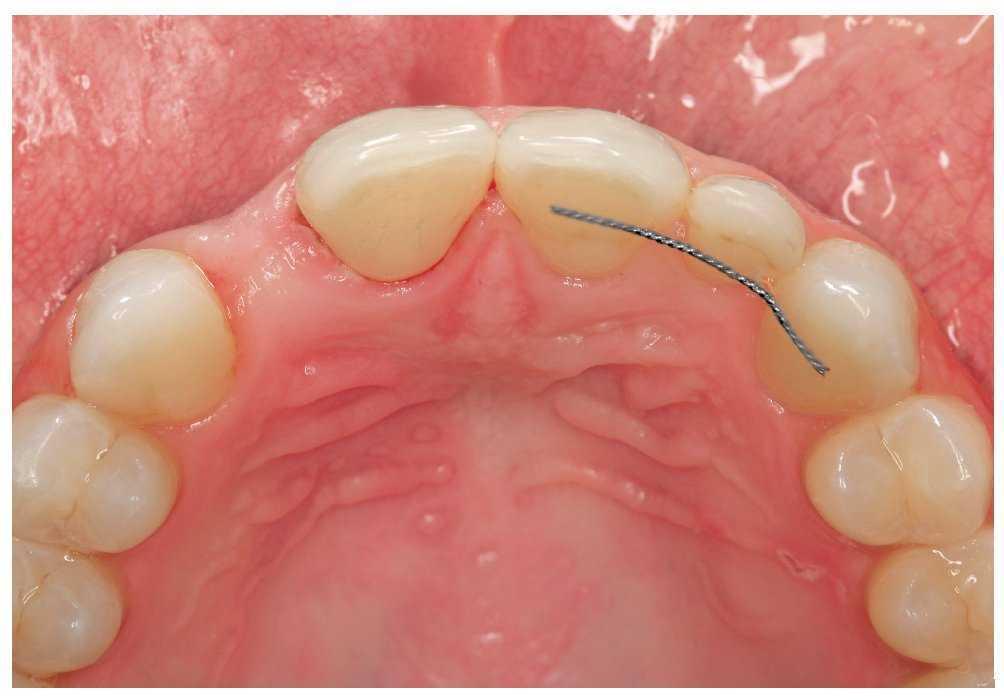

Figura 2a. Ausencia del diente 12, dientes adyacentes sin caries.

Figuras 2b y 2c. Puente adhesivo de cerámica sin metal de una aleta desde incisal (b) y vestibular (c).